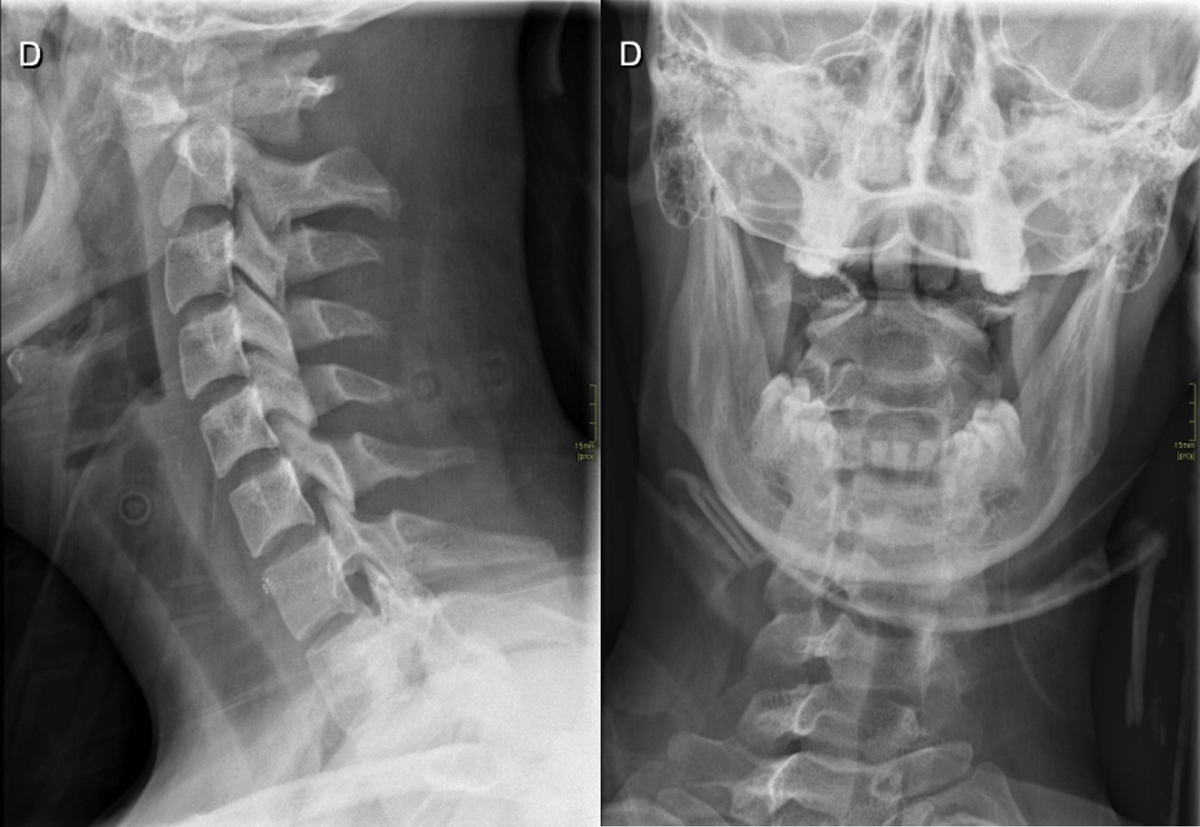

Traction anatomic repositioning preceded application of a rigid neck brace. A control radiograph demonstrated persistent rotation of C1 on C2 with one lateral mass of C1 lying anterior to the odontoid on the lateral projection and asymmetry of the lateral masses on anteroposterior open-mouth view (Figure 3). Repositioning was repeated with application of a halo vest, which again failed. Osteosynthesis of C1–C2 was successfully carried out.

Figure 3

Lateral and open mouth views radiographs.